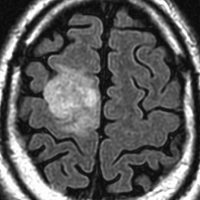

認知症で発症した60代男性の乏突起膠腫です。巨大で周囲の脳を圧迫する腫瘍でしたから,手術で部分摘出した後に放射線も化学療法も何もしないで経過観察しましたが,患者さんは社会復帰して仕事に戻れました。その後,無治療で13年が経過した時のMRIです。この13年間にほとんど大きくなっていません。このように高分化型とされる乏突起膠腫には,何もしないで様子を見ても長期間にわたって増大しない良性のものもあります。